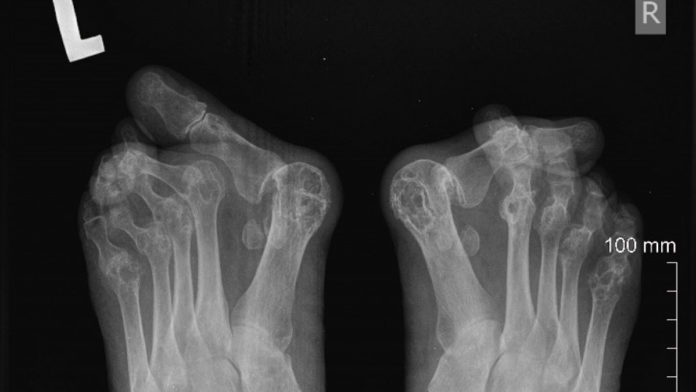

Postępujące RZS prowadzi do wielu zmian w obrębie stawów, najczęściej występującymi są: halluxy, palce młotkowate oraz płaskostopie podłużne i poprzeczne. Bardzo często dochodzi do zwichnięć w obrębie stawów paliczkowo-śródstopnych. Wszystko to składa się na problemy z przetaczaniem stopy, co może doprowadzać w konsekwencji do inwalidztwa.

Progressive RA leads to many joint changes. Halluxes, hammer-toes and longitudinal and transverse flat feet are the most common. Very often there are dislocations within the phalanges and metatarsal joints which may result in problems with the rolling of the foot, which may lead to disability as a consequence.